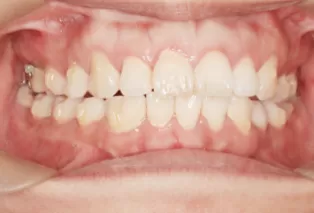

Photos intra-orales après traitement